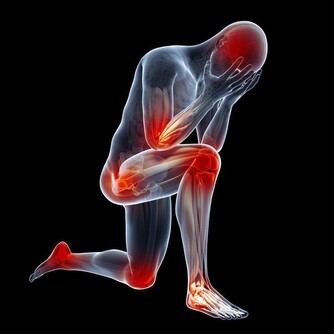

麻疹(Measles)是一種由麻疹病毒引起的急性傳染病,其傳染性極高,是目前全球公共衛生的重要議題之一。麻疹主要通過空氣中的飛沫傳播,也可以透過與受感染者的密切接觸傳播。其典型症狀包括高燒、咳嗽、流鼻涕、結膜炎(紅眼)以及紅色斑點狀皮疹,常被誤以為是普通感冒或過敏反應。然而,麻疹可能引發嚴重的併發症,包括肺炎、腦炎,甚至死亡。

麻疹病毒是目前已知傳染性最高的病毒之一,未接種疫苗者若暴露於患者周圍,約有90%的機率感染。病毒可透過空氣中的飛沫存活數小時,因此,即使短暫接觸也可能被傳染。